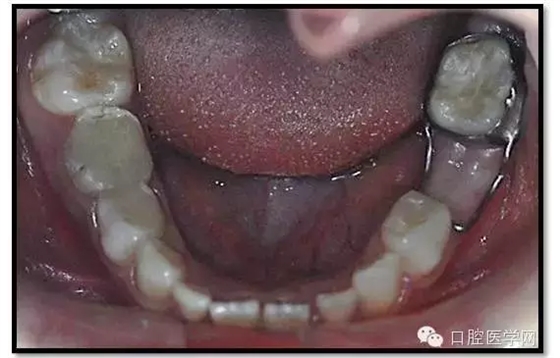

臨床檢查: 75OL齲洞, 舌側(cè)牙體完全劈裂斷端齊齦,探及大量軟化腐質(zhì)。頰側(cè)牙齦紅腫見瘺管,擠壓大量溢膿。叩(±),不松動(dòng)。X線:75根管空虛,牙根吸收約1/2,根尖周及根分歧大面積透射影,35發(fā)育4期,骨硬板尚連續(xù);51殘根,唇側(cè)牙齦瘺管,叩(±),不松動(dòng)。X線:51牙根吸收約1/2,根尖周低密度影。

85O、84DO充填體邊緣不密合,叩(±),不松動(dòng)。84頰側(cè)牙齦略紅腫。X線:84遠(yuǎn)中根及髓室底完全吸收,根分歧透射影,近中根內(nèi)側(cè)見外吸收,44上方骨硬板連續(xù)。85近中根完全吸收,髓室底吸收,根分岐透射影,遠(yuǎn)中根管內(nèi)見根充影像。45發(fā)育4期,骨硬板連續(xù)。